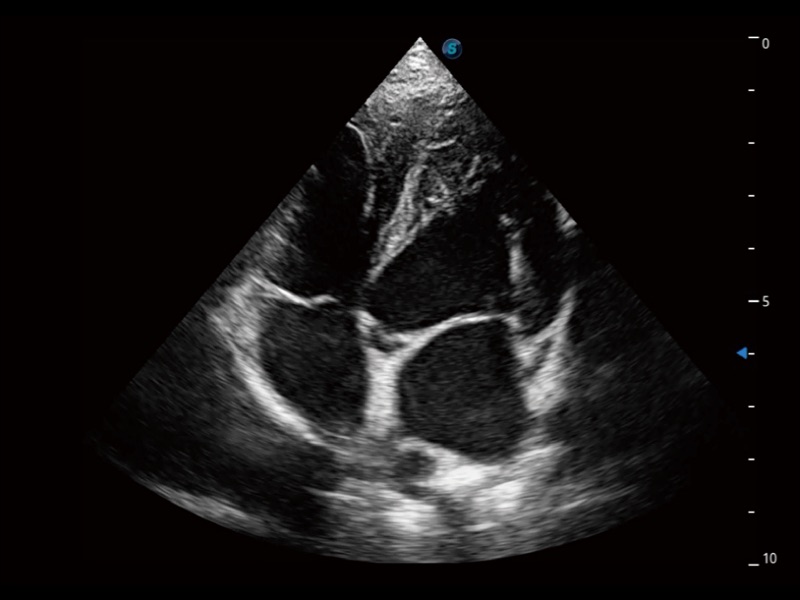

能够基于左心室壁追踪和辛普森法,自动计算射血分数,支持多个可移动点描迹,与手动测量相比,极大节省了动物医生的时间和精力。

具备多种协议可选,同时支持17阶段划分法和专业的SE报告。

当心脏测量结果超出正常范围时,可实时预警提示动物医生,减少疾病漏诊概率。